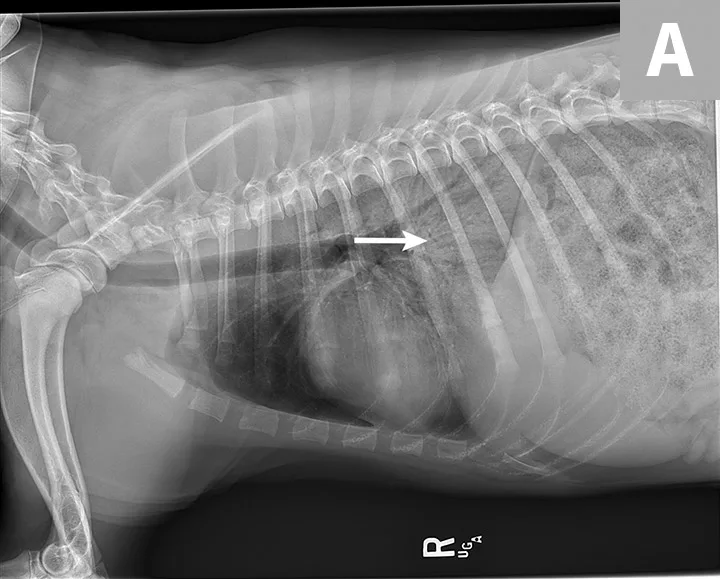

Blood pressure was decreased (85 mm Hg) on Doppler ultrasound. Oxygen saturation was initially 92% but increased to 98% with flow-by oxygen supplementation via mask (4 L/minute). Initial blood work showed mild hyperlactatemia (3.1 mmol/L; reference range, 0-2.5 mmol/L), packed cell volume of 54%, and total solids at 6.8 g/dL. Chest radiography was performed with oxygen supplementation and revealed a moderate to severe caudodorsal interstitial to alveolar lung pattern (Figures 1 and 2).

Radiograph showing air bronchograms consistent with noncardiogenic pulmonary edema (arrows). Atelectasis, which would be evident with shifting of the heart to the left or right, is not present.